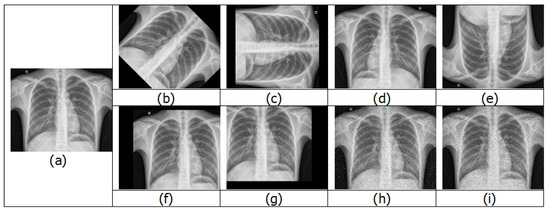

4.3. Data Augmentation

- (iv)